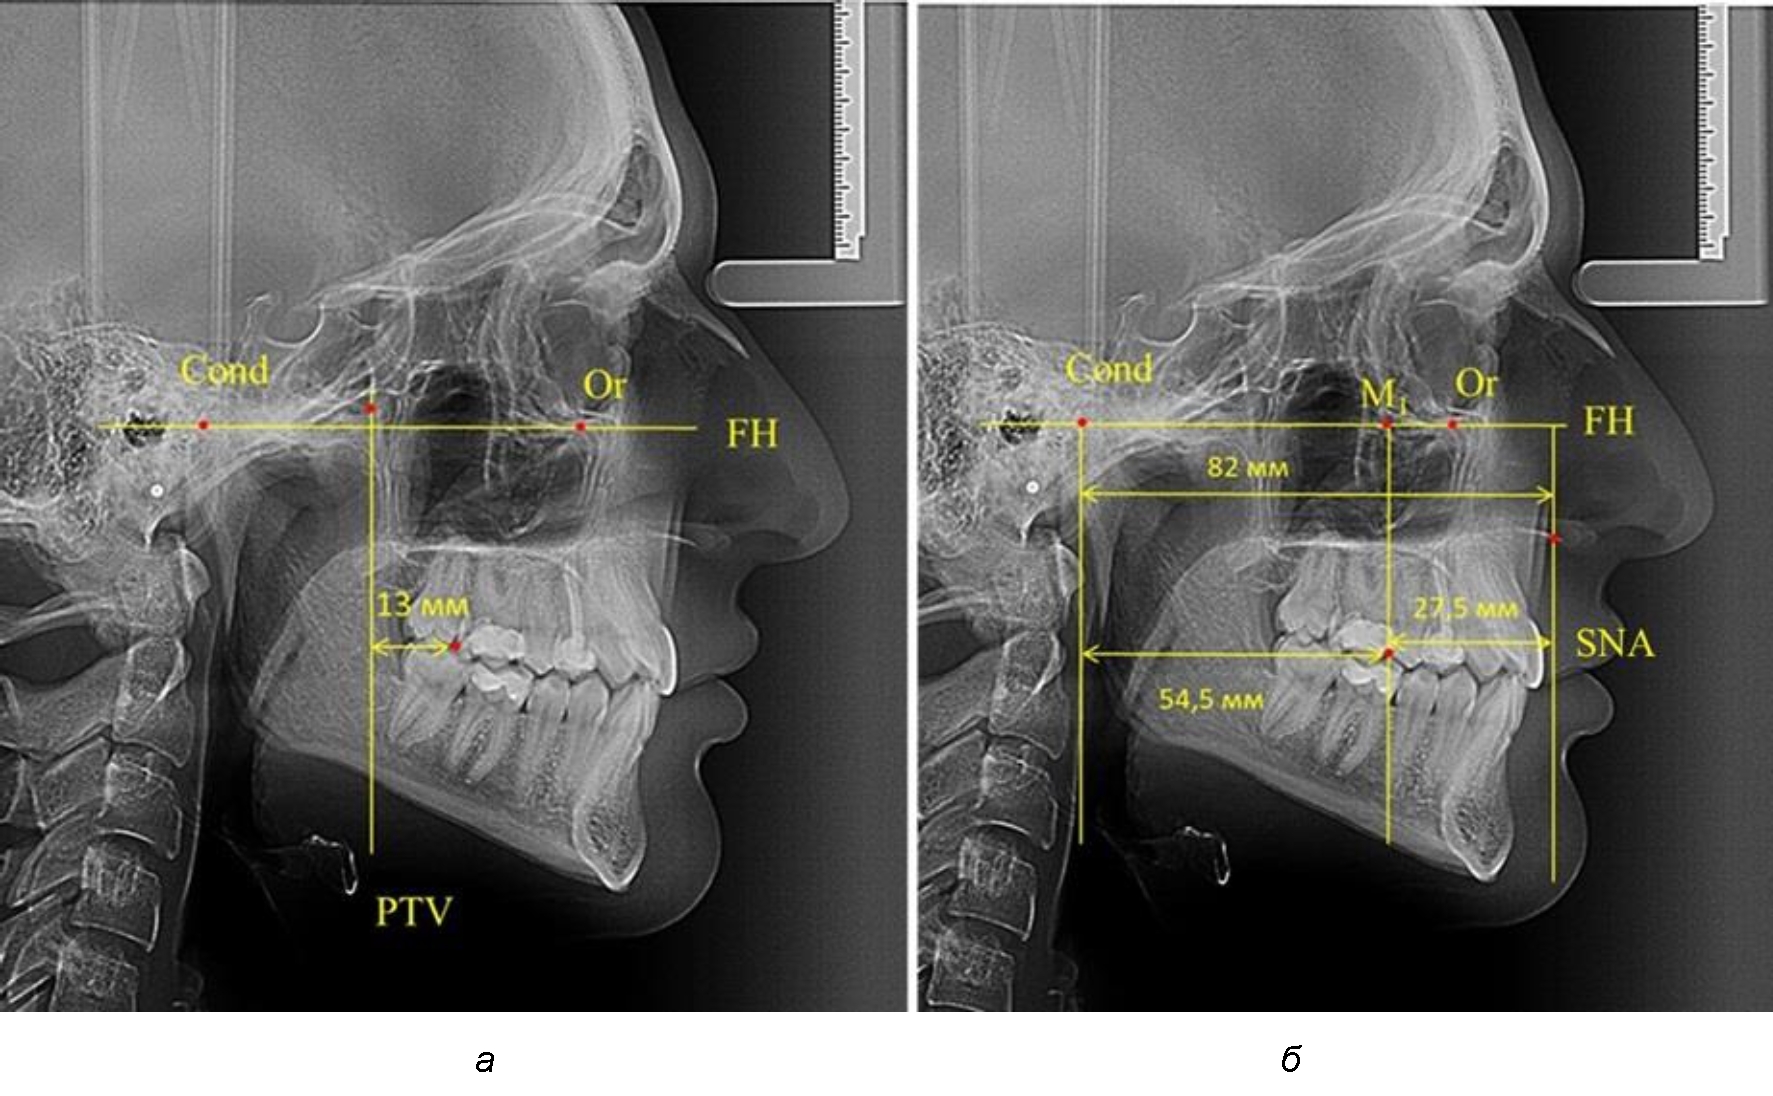

Рис. 1. Метод определения положения первых верхних моляров по Ralph E. McDonald (а) и по предложенному методу (б)

Согласно указанному методу на рентгенограммах проводили Франкфуртскую горизонталь. Учитывая мнения специалистов относительно ориентиров для построения и вариабельность положения наружного слухового прохода, в качестве задней точки использовали верхнюю выпуклость суставной головки нижней челюсти («Cond»). Передняя точка традиционно располагалась на нижнем крае глазницы и определялась как орбитальная точка Or.

Находили положение точки Pt, которая располагалась на пересечении нижнего края круглого отверстия и задней стенки крыловидно-верхнечелюстной щели, и перпендикулярно к Франкфуртской горизонтали проводили крыловидную вертикальную линию, которую принято обозначать как плоскость PTV. Расстояние от крыловидной вертикальной плоскости PTV до дистальной поверхности верхнего первого постоянного моляра определяло его положение, которое, по мнению R. E. McDonald, соответствовало возрасту пациента, увеличенному на 3 мм.

При проведении анализа к Франкфуртской горизонтали проводили передний и задний перпендикуляры. Передний спинальный перпендикуляр проходил через выступающую точку передней носовой ости (spina nasalis anterior – SNA), а задний суставной перпендикуляр опускали из кондилярной точки Cond. Молярный перпендикуляр проводили через медиальную поверхность первого постоянного моляра. Указанная вертикаль отделяла замещающие зубы постоянного прикуса от добавочных зубов (постоянных моляров), что вполне логично для анализа положения первых постоянных моляров в гнатическом комплексе (рис. 1).

Если метод R. E. McDonald позволял оценить только положение первых постоянных верхних моляров, то предложенный метод учитывал сагиттальные индивидуальные размеры гнатического отдела лица и определять соотношение межу его размерами в передней и задней части.

Так, при расстоянии от крыловидной вертикальной плоскости PTV до дистальной поверхности верхнего первого постоянного моляра в 13 мм сагиттальный размер гнатического отдела был 82 мм. При этом отношение кондилярно-спинального расстояния к кондилярно-молярному размеру (54,5) было близким к коэффициенту 1,5, что представлено на рис. 2.